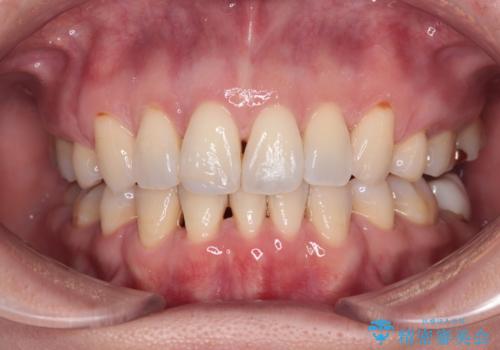

反対咬合の改善 途中で出産をしながらワイヤー矯正

- 前歯の隙間と反対咬合を気にして来院された患者様です。

咬合力が強く、反対咬合の改善に時間がかかりましたが、その後はスムーズに進めることができました。

途中、妊娠と出産があり、治療が中断したため、治療期間は延びましたが、出産も矯正治療も無事に終えることができました。